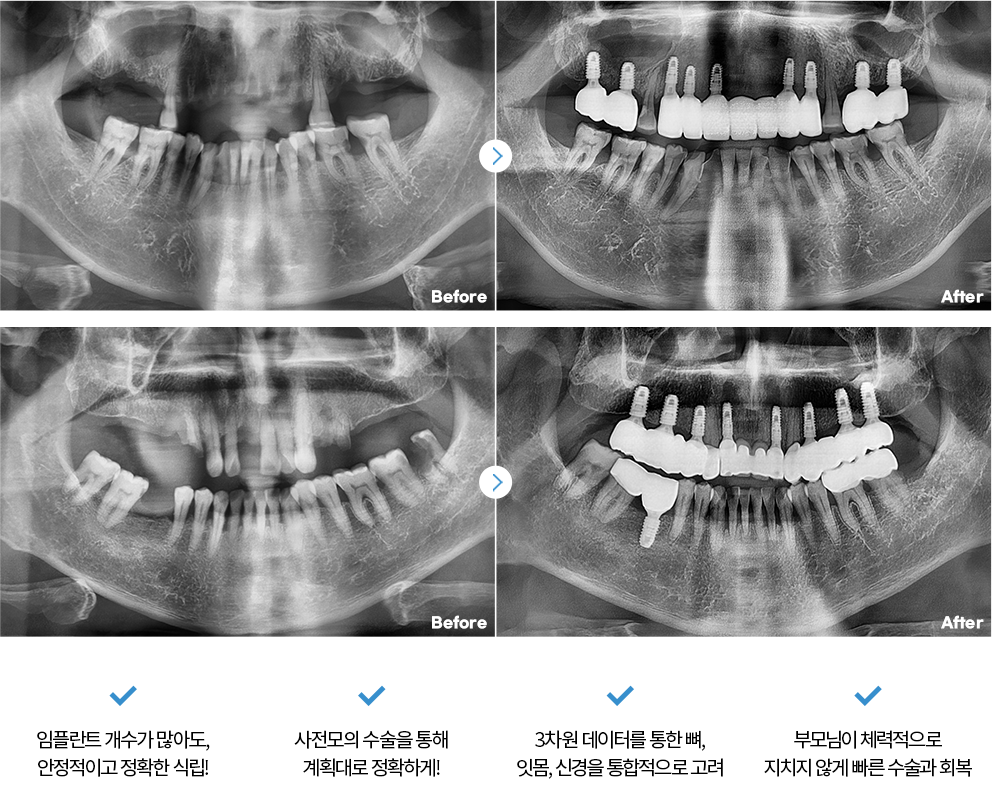

Before & After

치료 후 1년이 지난 모습입니다.

- 전체보기

- 임플란트